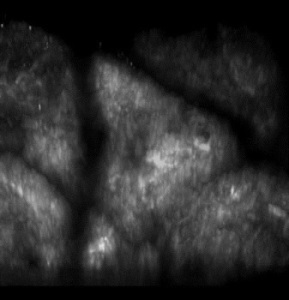

For their study, the researchers performed in vivo two-photon imaging on the forearm of healthy subjects before and forty days after the laser treatment. De novo production of new collagen, as well as an increase in the amount of dermal amorphous component, was found within 40 days from the laser treatment. Visual inspection of the acquired SHG images of dermis by experienced dermatologists demonstrated a stronger collagen synthesis and remodeling on older subjects, whereas the modifications were minimal on younger subjects. The age-dependent effectiveness of the treatment was confirmed by a quantitative spectral analysis, based on the second-harmonic to autofluorescence aging index of dermis (SAAID), which is a recognized scoring method for skin aging assessment by means of non-linear microscopy. In addition, a pattern analysis of SHG images using grey-level co-occurrence matrix (GLCM) was carried out, a well-established method for scoring collagen organization in skin.